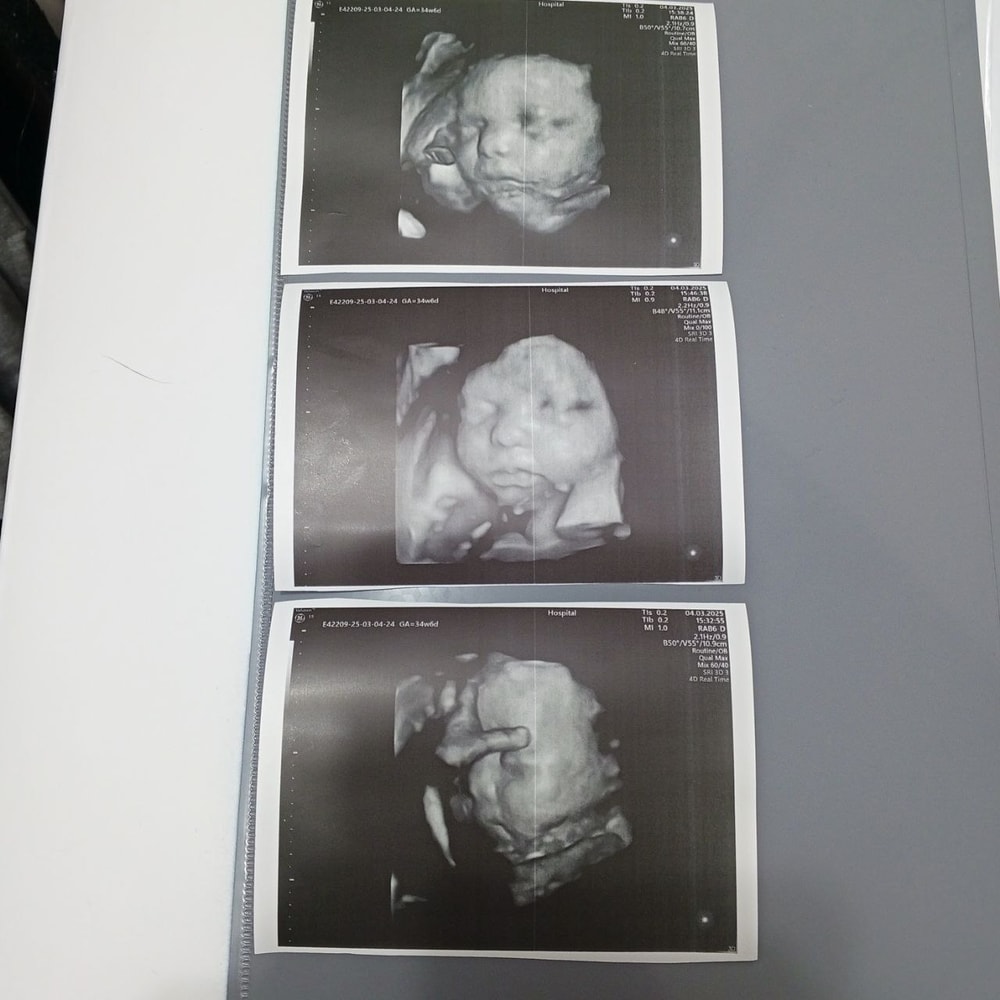

Дочка с ногами у лица, щекой на плаценте, другой щекой на ручке. Один нос торчит!) Но был момент, когда ручку убрала она от лица и картинка сложилась:))) Ничего особо не увидели( Надо было раньше ехать(( Но посмотрели все органы, каждый орган! Все на месте, все хорошо, лишнего ничего не выросло!)

РОСТ 37СМ

ВЕС 1150Г

Соответствует 28.2 неделям)) У меня 27.4)